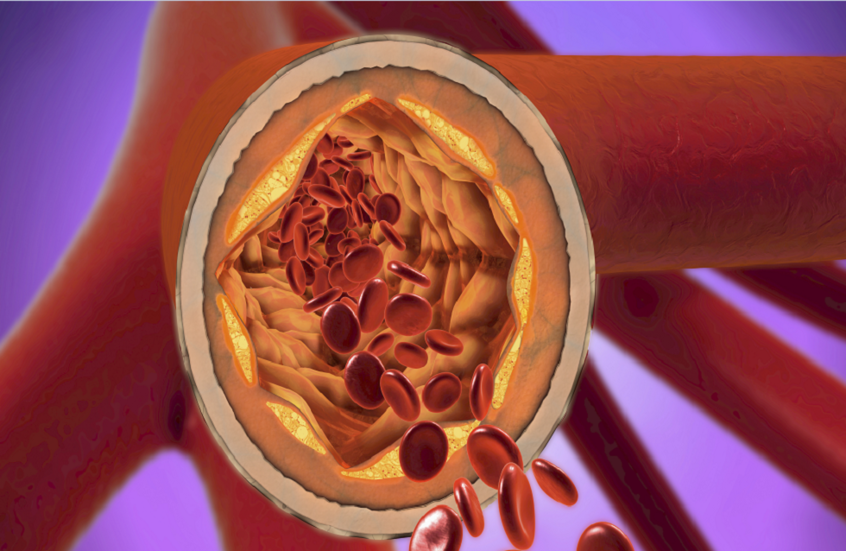

كشف باحثون عن قرص دواء جديد يخفّض بشكل ملحوظ مستوى الكوليسترول الضار (LDL) لدى الأشخاص الذين يظلون معرضين لخطر الإصابة بالنوبات القلبية رغم تناولهم أدوية الستاتينات.

ويعمل قرص الدواء على مساعدة الجسم في التخلص من الكوليسترول بطريقة لا يمكن تحقيقها حاليا إلا بواسطة الأدوية التي تُعطى عن طريق الحقن، مثل مثبطات بروتين PCSK9 (ينتجه الكبد ويلعب دورا في تنظيم مستويات الكوليسترول الضار (LDL) في الدم). وتثبّط الستاتينات مثل "ليبيتور" و"كريستور" أو بدائلها الجنيسة منخفضة التكلفة، إنتاج الكبد للكوليسترول، وهي حجر الزاوية في العلاج، إلا أن كثيرا من المرضى يحتاجون إلى دعم إضافي للوصول إلى مستويات الكوليسترول الموصى بها طبيا.